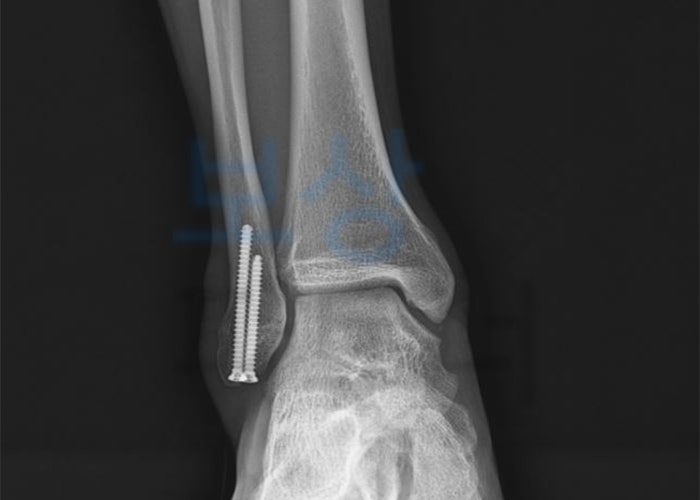

진단 병명은 외측 복사의 골절, 즉 발목 바깥쪽 복사뼈의 골절이었습니다. 수술은 관혈적 정복 및 금속 나사못 내고정술을 시행하였는데요, 직접 다친 부위를 절개하여 눈으로 확인 후 나사못이나 핀 등을 이용하여 고정하는 방법입니다. 발목 같은 경우는 체중이 실리는 중요한 관절이라 확실한 골 유합이 꼭 필요한 부위죠.

위 엑스레이 사진을 보시면 나사못으로 발목 외측 부분을 고정해놓은 것을 확인하실 수 있습니다. 보험약관상 다리의 후유장해에 해당하는 기준은 다음과 같습니다. (2018년 4월 1일 이후 최신 약관) 위의 장해 기준에서와 같이 관절의 운동 범위 제한에 따라 후유장해보험금을 청구할 수 있는 금액이 결정되는데, 발목 복사뼈 다친 경우에는 움직임이 제한되기가 쉽기 때문에 꼭 한번 해당되는지의 여부를 알아보셔야 합니다.